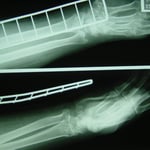

〇右前腕骨骨折(スミス骨折)

自転車で転倒し手をつき手首を骨折しました。

病院でレントゲン検査の結果、3か所の骨折が認められました。

後日手術の予定が組まれ,全身麻酔下で行うことを聞かされた時に非常に困惑し、セカンドオピニオンとして手の専門外科に相談に行かれました。

ここでも手術療法が妥当だと日程を組むことになってしまいました。

手術をしないで治ることはできないかとインターネットで調べ当院を知り相談に来られました。

骨折により保存治療が出る場合と手術療法が必須の場合があります。

しかし最近では一般的な骨折(転倒などにより起きる定型的な骨折)でも積極的に手術を勧められるケースが多くなってきています。特に総合病院では手術の傾向があるように思われます。

確かに骨折部位をプレートとビスにより内固定すれば強固な固定ができますが、患者さんのリスクとQOLの低下はどのようなところにあるでしょうか? 細かな説明がなく術後の経過観察はレントゲン検査の結果のみで評価し、日常の問題をよく聞いてもらえません。リハビリは理学療法士に任せ、術後の処置は看護師の役割になっています。

今回事情を聴き、整形外科の先生と相談をし当院で処置と経過観察をすることになりました。

整骨院の従来の固定法である副木(シャーレ)と包帯を駆使して患者さんに負担の少ない固定をしました。

毎日 固定具を外し患部の浮腫の除去、血行維持、清拭、超音波治療を行います。固定具に不自由があれば

修正をしました。 このように毎日患者さんに触れ、不安を聞くことにより自律神経も安定し良い結果につながるのです。

経過は非常に良好で転移(骨のずれ)もなく約2か月で薬剤師の仕事に復帰されました。